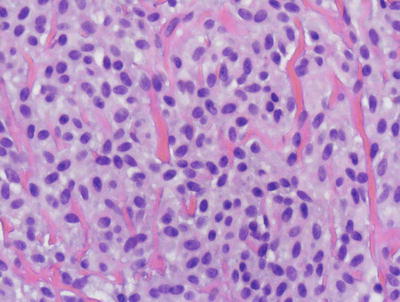

In LCH, the epidermis demonstrates focal parakeratosis overlying varying degrees of spongiosis that is diffuse throughout the epidermis. In most cases, there is abundant exocytosis of Langerhans cells into the epidermis (Fig. 22.3). Langerhans cells can usually be identified based upon cytologic features that include reniform-shaped, grooved, or folded nuclei and abundant cytoplasm (Figs. 22.4 and 22.5). Anti-CD1 a immunohistochemistry is useful in cases when the nature of the infiltrating cells is not readily apparent. Intraepidermal eosinophils are also quite common. Cytologic atypia and significant mitotic activity are rarely encountered. Some cases fail to demonstrate exocytosis of Langerhans cells into the dermis. Treatment with topical corticosteroids prior to biopsy may also suppress exocytosis and mask the diagnostic features.

Fig. 22.4

Langerhans cell histiocytosis is comprised of sheets of Langerhans cells with grooved or reniform nuclei and ample eosinophilic cytoplasm. Eosinophils are usually present throughout the infiltrate

Fig. 22.5

Langerhans cells have a characteristic reniform nuclei, often with a grooved appearance. They are readily identifiable on routine H&E sections in most cases, although immunostains can be used to confirm the histologic impression